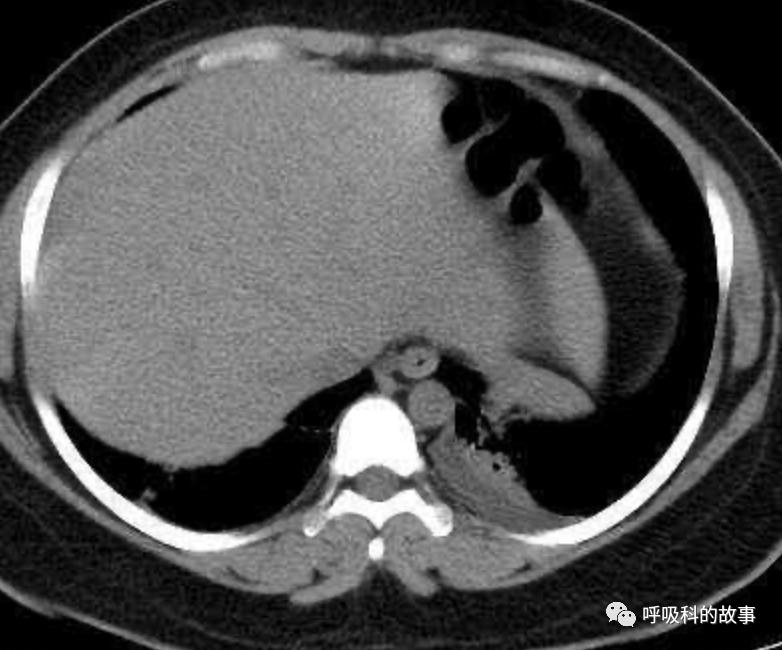

患者发热后行胸部CT检查(6月21日,住院第13天),可见两下肺有条片影,当时考虑是肺炎引起的发热。

可是在6月26日(往院第18天)仍持续发热的情况下复查肺部CT,肺部病灶已明显吸收了。那么患者发热的原因到底是什么呢?为什么患者高热的情况下血白细胞不升反降,C反应蛋白也没有明显增高?这个时候消化科医生也迷茫了,这可怎么办?于是请感染科和呼吸科医生一起会诊,共商计策。